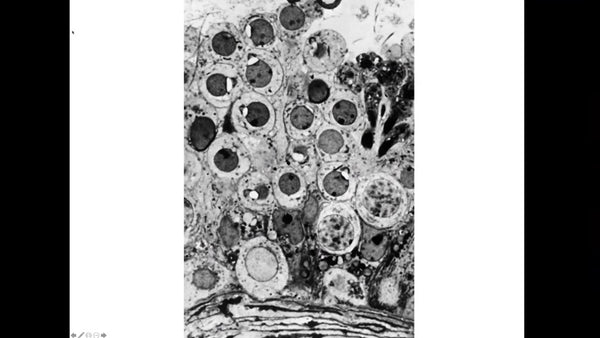

Surgically Removed Sperm, a Global View